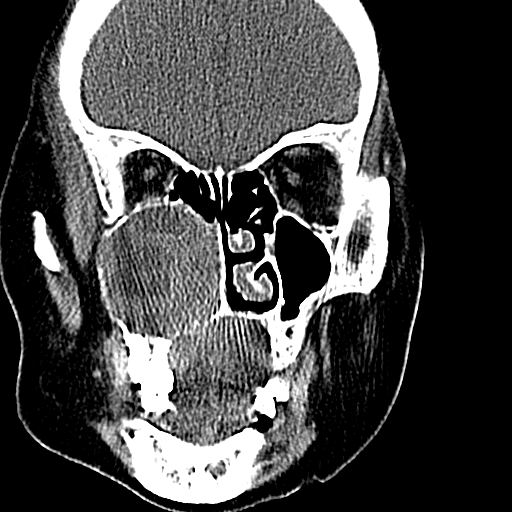

标题: CT19708:单侧上颌窦病变

老年患者,女。鼻塞多年。

考虑右侧上颌窦良性占位性病变,粘液囊肿可能性大;建议活检。

膨胀性生长,且骨质无破坏,说明时间久,良性;从密度,边缘看,内部还见坏死区,应该是实性肿瘤,定性,影像学无绝对的特异性

病灶密度很不均匀,骨壁膨胀中有断裂,考虑内翻乳头状瘤可能性大,粘液囊肿不排除

膨胀性生长,且骨质无破坏,说明时间久,良性;从密度,边缘看,内部还见坏死区,应该是实性肿瘤,定性,影像学无绝对的特异性,考虑内翻性乳头状瘤可能